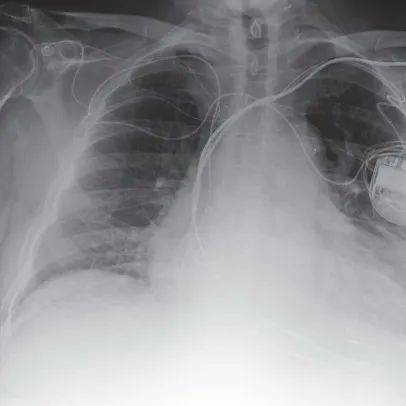

LLaVA-Rad 专注于胸部 X 光(CXR)成像,旨在为医学影像检查自动生成高质量放射学报告。该模型在七个不同来源的数据集上进行了训练,共包含 697435 对放射学图像 – 报告,并在仅有结构化标签时利用 GPT-4 进行报告合成。